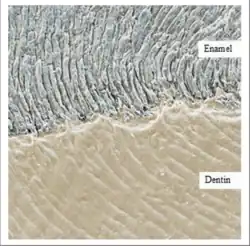

Enamel

Enamel is the outermost and hardest tissue in the human body.[4] It consists of approximately 96% inorganic material, primarily in the form of carbonated hydroxyapatite crystals, with the remainder composed of organic matrix and water.[5] Its main function is to protect the underlying dentine and aid in food breakdown through mastication.[6]

Enamel is formed during amelogenesis, a two-stage process beginning with the secretion of an organic matrix by ameloblasts near the dentinoenamel junction (DEJ).[5] Once mineralisation reaches 96%, enamel formation is complete, and no further deposition occurs due to the degeneration of ameloblasts.[7][5]

At the microscopic level, enamel has a complex structure composed of enamel rods and interrod enamel, arranged in a prism-like pattern which contributes to its density and mechanical strength.[5]

Dentine

Dentine lies beneath the enamel and forms the bulk of the anatomical crown. It supports the enamel and protects the innermost pulp chamber.[7][6] Composed of 70% inorganic material, 20% organic matrix (mainly collagen), and 10% water, dentine is resilient and capable of absorbing functional stresses.[8]

The structure of dentine includes dentinal tubules that extend from the enamel-dentine junction to the pulp. These tubules are surrounded by peritubular and intertubular dentine, contributing to its mechanical properties and sensitivity.[5][8]